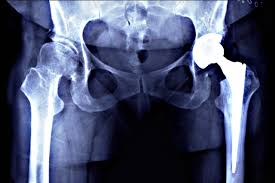

Modern surgical approaches have made quick recovery hip surgery possible. Techniques such as minimally invasive hip replacement reduce tissue trauma and promote faster healing. In Bhopal, hospitals like Varunam Hospital use advanced tools and implants to optimize surgical outcomes. Furthermore, Dr. Utsav Agrawal monitors surgical precision and ensures adherence to best practices, reducing post-operative complications. Consequently, patients experience improved mobility and reduced recovery time.